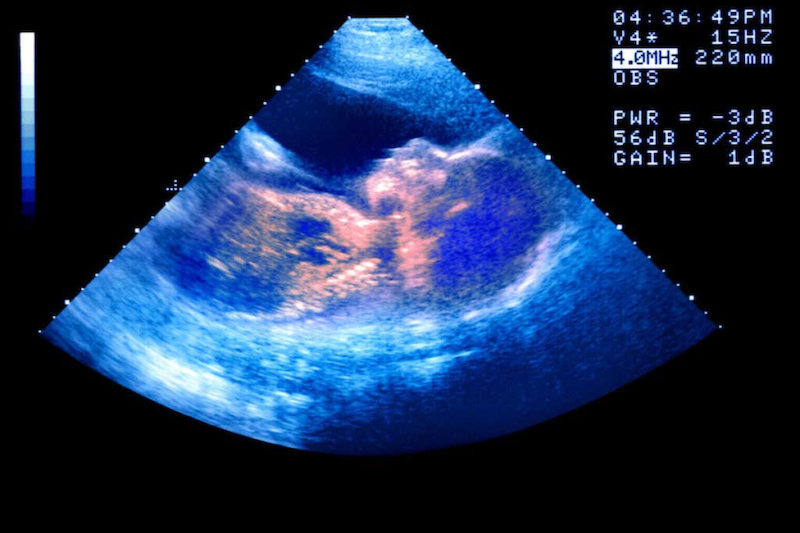

The researchers show first that women over 35 are more likely to have more advanced prenatal care. The most striking graph is on detailed ultrasound scans; I’ve included it below. It is pretty clear from this picture that when you tick over that age-35 cutoff (the x-axis of this graph is denoted in days around the 35th birthday), you get more scans.